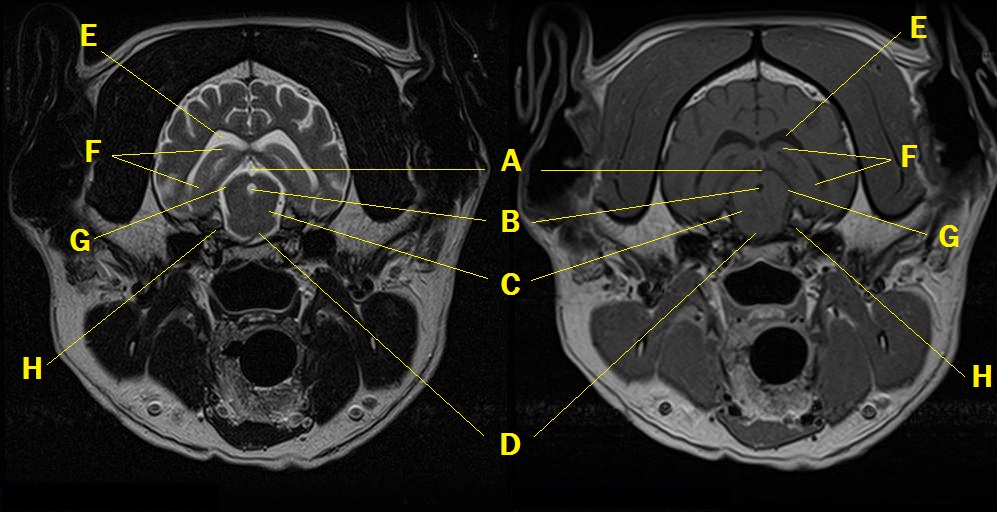

MRI anatomy 8

Q. Identify the structures labeled below:

A.

A. subarachnoid space

B. 3rd ventricle

C. mesencephalic tegmentum

D. rostral part of the transverse fibers of the pons

E. lateral ventricle

F. hippocampus

G. brachium of caudal colliculus

H. trigeminal nerve